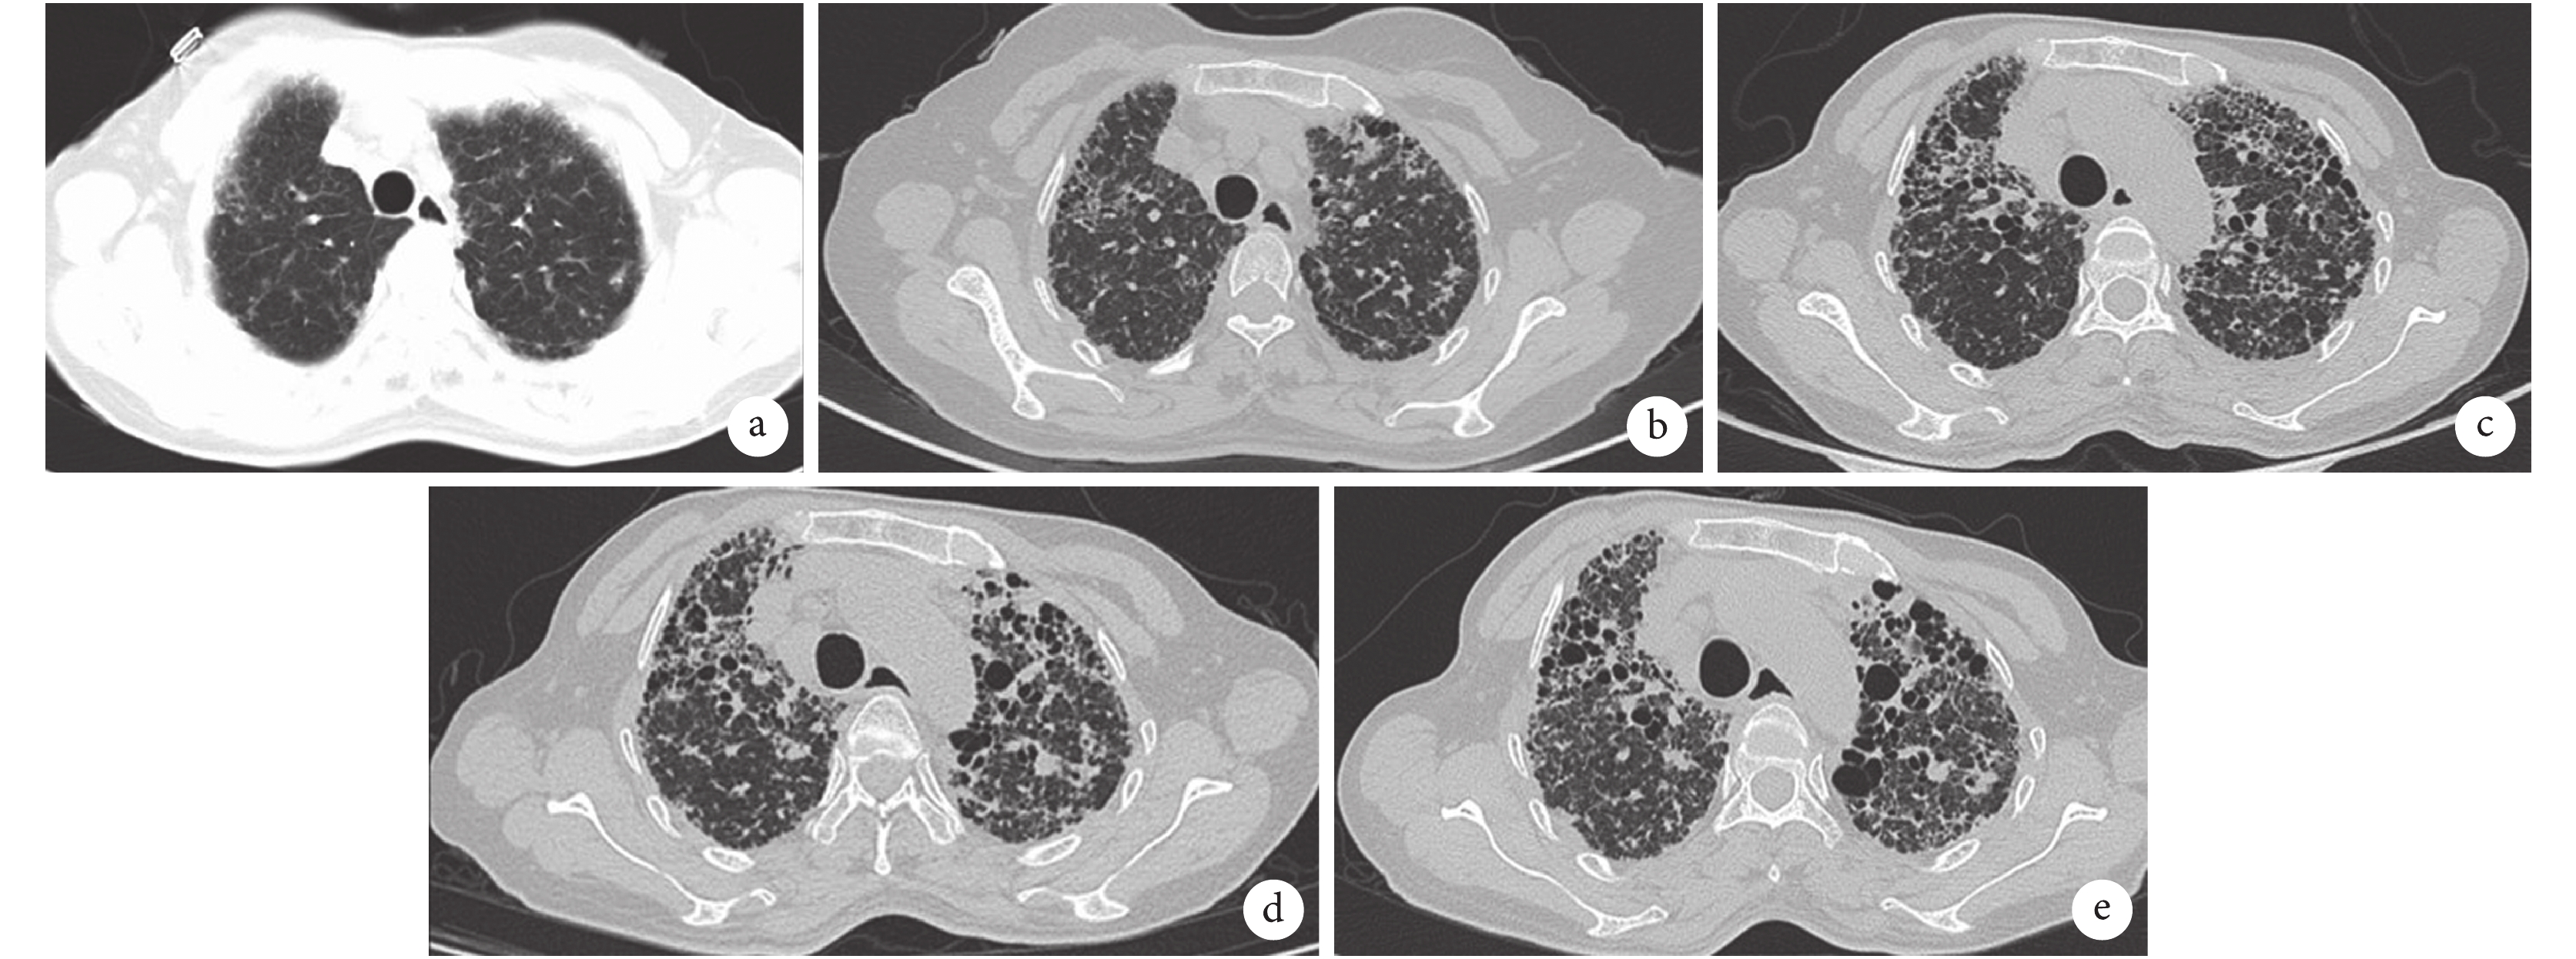

a. 2010-08-25,雙肺間質性改變,散在慢性感染灶;b. 2016-10-08,雙肺間質性改變,散在磨玻璃影和網格狀改變;c. 2019-03-19,雙肺間質性肺炎伴散在感染灶,胸膜粘連,蜂窩肺明顯;d. 2019-06-13,雙肺磨玻璃影、網格狀影較前無明顯改變;e. 2019-09-27,蜂窩肺。

完善實驗室檢查:血氣分析(吸氧濃度 33%):pH 7.433,PaO2 106.4 mm Hg(1 mm Hg=0.133 kPa),PaCO2 41.6 mm Hg。血沉 111.0 mm/1 h。血常規、降鈣素原、肝腎功能、電解質、凝血功能常規、尿鈉素、心肌標志物、輸血前全套、腫瘤標志物、甲功、糖化血紅蛋白、尿常規、大便常規未見明顯異常。感染相關指標:肺炎支原體抗體 IgG 70.42 RU/mL(參考值<20 RU/mL),肺炎衣原體 IgG 53.63 RU/mL(參考值<20 RU/mL);EBV-DNA、CMV-DNA、TORCH-IgM、痰涂片、痰培養、G 試驗、GM 試驗未見明顯異常。免疫相關指標:外周血 T 細胞亞群:CD3+ 細胞亞群 42.40%,CD4+ 細胞亞群 29.00%,CD8+ 細胞亞群 11.50%,CD4+/CD8+ 比值 2.52(參考值 0.97~2.31);抗核抗體譜:抗核抗體(ANA)+1∶100(斑點型);免疫全套、抗 CCP 抗體、抗角蛋白抗體、ANCA、冷凝集素試驗未見明顯異常。胸部 CT 示:雙肺間質性肺炎伴散在感染灶,部分區域呈蜂窩肺樣改變,胸膜粘連;肺門及縱隔淋巴結部分增大(圖 1c)。肺功能示:極重度限制性通氣功能障礙,中度肺氣腫,通氣儲備功能重度下降,過度通氣,肺通氣功能極重度受損。患者配合欠佳,彌散功能無法檢測。經支氣管鏡冷凍肺活檢(TBLC)病理示:細支氣管擴張伴黏液栓形成,其周見較多細支氣管化生;肺組織結構破壞,間質增寬伴淋巴細胞浸潤及聚集,腔內見少量嗜酸性粒細胞及中性粒細胞浸潤;目前未見肉芽腫,未見纖維母細胞灶(圖 2)。免疫組織化學示:P63(基底細胞+)、CK5/6(上皮+)、WT-1(間皮+)、D2-40(間皮+)。綜上,傾向慢性過敏性肺泡炎。綜上,明確診斷過敏性肺炎,給予強的松 30 mg/次,1 次/d,此后門診隨訪。2019 年 6 月 13 日(服用強的松 3 個月余),患者自覺咳嗽、呼吸困難癥狀加重,復查胸部 CT 提示雙肺磨玻璃影、網格狀影較前無明顯改善(圖 1d),遂建議強的松逐漸減量至停用,其后給予吡非尼酮 100 mg/次,3 次/d,逐漸加量至 300 mg/次,3 次/d,服用 2 個月余,患者呼吸困難癥狀仍未見好轉,自行停用吡非尼酮。建議行肺移植,患者及家屬拒絕。規律隨訪 6 個月,現失訪。

過敏性肺炎是易感人群反復吸入具有抗原性的有機粉塵或化學物質,引起肺部的變態反應性炎癥反應。通常,接觸不耐受的變應原 4~12 h 后,過敏性肺炎患者可出現發熱、寒戰、干咳、呼吸困難、全身不適等癥狀,數小時內緩解。及時發現致病變應原,停止吸入,可自行痊愈。長期反復吸入不耐受的變應原會導致肺部出現明顯的結構受損,影響肺功能,患者表現為進行性呼吸困難、干咳、乏力、體重減輕[3]。本例患者病程長達 9 年,以干咳為主要表現,胸部影像學提示起病初期以結節、磨玻璃及斑片為主,隨著病情進展,部分區域呈蜂窩肺改變。由于患者在國內居家期間發病,其本人無特殊不良嗜好,也未飼養寵物,整個病程中未發現確切的變應原物質。

過敏性肺炎患者典型 HRCT 表現為以中上肺為主的彌漫小葉中心結節、斑片影或磨玻璃影、馬賽克征[4]。典型病理改變為三聯征,即以支氣管為中心的淋巴細胞性間質性肺炎、細支氣管炎、形成不良的肉芽腫[5]。BALF 中可見淋巴細胞比例升高[6]。若未及時脫離變應原,疾病緩慢進展,HRCT 表現常為明顯的纖維化,呈斑片狀或圍繞支氣管血管,常伴有牽拉性支氣管擴張,可有蜂窩肺改變、小葉間隔增厚等表現[7-8]。典型病理學改變為以氣道為中心的間質纖維化及形成不良的非壞死性肉芽腫,可伴有細支氣管周圍化生、機化性肺炎等表現[9]。本例患者 BALF 淋巴細胞比例高達 39%,TBLC 肺組織病理提示細支氣管周圍化生、間質增寬伴淋巴細胞浸潤,未見肉芽腫及纖維母細胞灶,與文獻報道基本一致。Salisbury 等[10]和 Wang 等[11]的研究表明影像學出現蜂窩肺、網格狀改變及牽拉性支氣管擴張與過敏性肺炎患者的生存期縮短相關。這能解釋本例患者在確診后接受糖皮質激素抗炎治療及吡非尼酮抗纖維化治療后反應差,病情仍然進展。